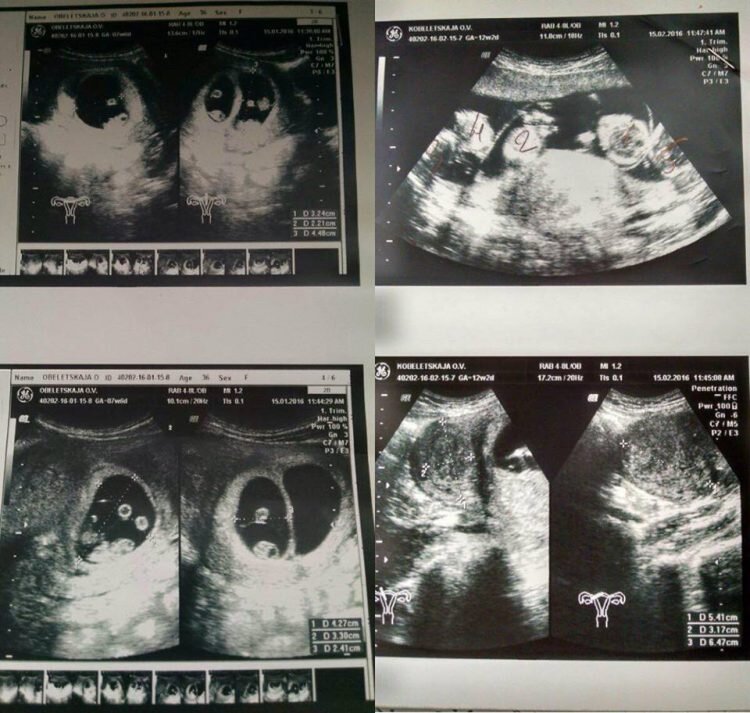

Живущая в Одессе Оксана уже имеет одну прекрасную дочь и в возрасте 36-ти лет, узнав, что в семье снова ожидается прибавление, была рада как никогда. Они с мужем всегда хотели второго ребенка и это была отличная новость для них обоих, но то, что произошло позже, потрясло не только их, но и весь мир! Истории про двойняшек и, тем более, тройняшек казались для Оксаны и ее мужа сказкой, в роду никогда такого не случалось, и они до последнего думали, что такие истории не про них. Но отправившись на плановый осмотр в больницу, ее врач сообщил ей новость, которая повергла ее в шок. «Все было как у всех: голый живот, гель и датчик. Но когда доктор начала смотреть в экран, у нее сильно изменилось лицо, и я не на шутку испугалась,» — вспоминает Оксана. — «Помню как она начала вслух считать количество плодов и приговаривала, что за такое мне должны подарить дом у моря… Итак, по итогу по результатам УЗИ выяснилось, что Оксана ждет пятерняшек! Такой редкий случай, когда без искусственного опл